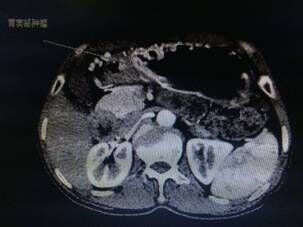

我院胃腸外科今年3月收治一名男性患者,以反復(fù)腹痛7月入院,CT提示胃竇部及乙狀結(jié)腸占位性病變(分別見圖1、2),行內(nèi)窺鏡活檢分別考慮胃腺癌以及乙狀結(jié)腸絨毛狀腺瘤,不排除惡變傾向。為改善患者生存率,減少創(chuàng)傷,手術(shù)團(tuán)隊(duì)決定充分發(fā)揮腹腔鏡技術(shù)優(yōu)勢,采用腹腔鏡下一期同時(shí)切除胃、結(jié)腸病變,由于患者乙狀結(jié)腸病變惡性診斷不明確,根據(jù)腫瘤根治的原則,先處理乙狀結(jié)腸。手術(shù)當(dāng)中依據(jù)冰凍切片,在腹腔鏡下首先完成乙狀結(jié)腸癌根治,后行腹腔鏡下遠(yuǎn)端胃癌根治術(shù)。一次微創(chuàng)手術(shù),切除兩個(gè)腫瘤,免除了患者傳統(tǒng)剖腹手術(shù)及二次手術(shù)的創(chuàng)傷,縮短了住院時(shí)間,術(shù)后恢復(fù)快,降低了患者住院費(fèi)用。

圖片1                               圖片2